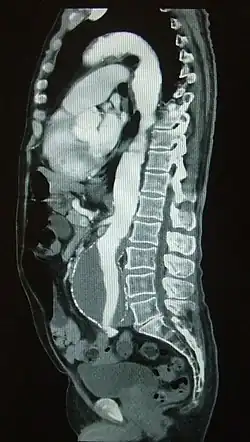

Компьютерная томографическая ангиография (КТ-ангиография, КТА) позволяет получить подробное изображение кровеносных сосудов и оценить характер кровотока. После проведения компьютерной томографии с внутривенным контрастным усилением производится анализ полученных данных с применением специальных алгоритмов реконструкции изображений.

Исследование проводится в амбулаторных условиях. Пациент укладывается на стол компьютерного томографа и в венозный катетер (как правило, установленный в локтевую вену) с определённой скоростью вводится контрастное вещество на основе йода в объеме ~100 мл. В процессе введения контрастного вещества делают серию сканирований исследуемого участка рентгеновскими лучами. При распространении контрастного вещества по сосудистой системе, сосуды становятся более контрастными. После этого посредством мультипланарной и трёхмерной компьютерной реконструкции врач-рентгенолог анализирует полученные изображения.